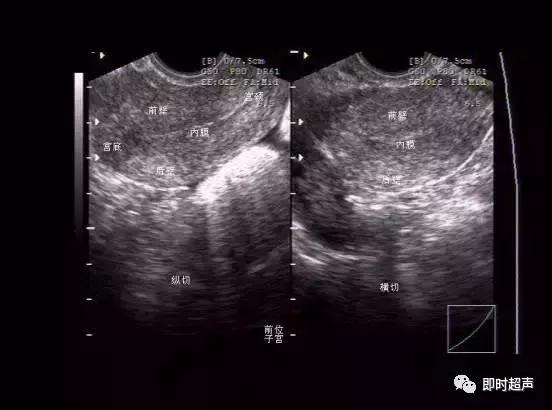

图像方位的确认

TVCD超声声像图

1.子宫增大,体积增大,轮廓不规则,后壁增厚,内膜线前移

2.异位的肌层回声增强或呈网状回声内膜线前移,内膜线居中,或稍偏前;

3.宫体回声分布不均;

4.若为腺肌瘤,则形成局部团块,边界欠清晰。